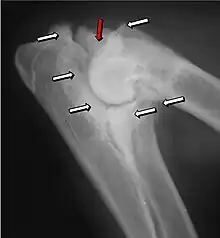

Most primary lesions are related to osteochondrosis, a disease of the joint cartilage, and osteochondritis dissecans (OCD), the separation of a flap of cartilage on the joint surface. Other common causes of elbow dysplasia include an ununited anconeal process (UAP) and fragmented or ununited medial coronoid process (FCP or FMCP).[1]

In OCD, the normal change of cartilage to bone in the development of the joint fails or is delayed. The cartilage continues to grow and may split or become necrotic. The cause is uncertain, but possibly includes genetics, trauma, and nutrition (including excessive calcium and decreased vitamin C intake).[4] OCD lesions found in the elbow at the medial epicondyle of the humerus are caused by disturbed endochondral fusion of the epiphysis of the medial epicondyle with the distal end of the humerus, which may in turn be caused by avulsion of the epiphysis.[5] Specific conditions related to OCD include fragmentation of the medial coronoid process of the ulna (FMCP) and an ununited anconeal process of the ulna (UAP). All types of OCD of the elbow are most typically found in large breed dogs, with symptoms starting between the ages of 4 and 8 months.[4] Males are affected twice as often as females. The disease often affects both elbows (30 to 70 percent of the time), and symptoms include intermittent lameness, joint swelling, and external rotation and abduction of the paw.[6] Osteoarthritis will develop later in most cases.

UAP is caused by a separation from the ulna of the ossification center of the anconeal process.[7] FMCP is caused by a failure of the coronoid process to unite with the ulna.

Diagnosis is through x-rays, arthroscopy or CT (computed tomography). In cases with significant lameness, surgery is the best option, especially with UAP. However, conservative treatment is often enough for cases of FMCP and OCD of the medial humeral epicondyle. The dogs are exercised regularly and given pain medication, and between the ages of 12 and 18 months the lameness will often improve or disappear.[4] Control of body weight is important in all cases of elbow dysplasia, and prevention of quick growth spurts in puppies may help to prevent the disease.